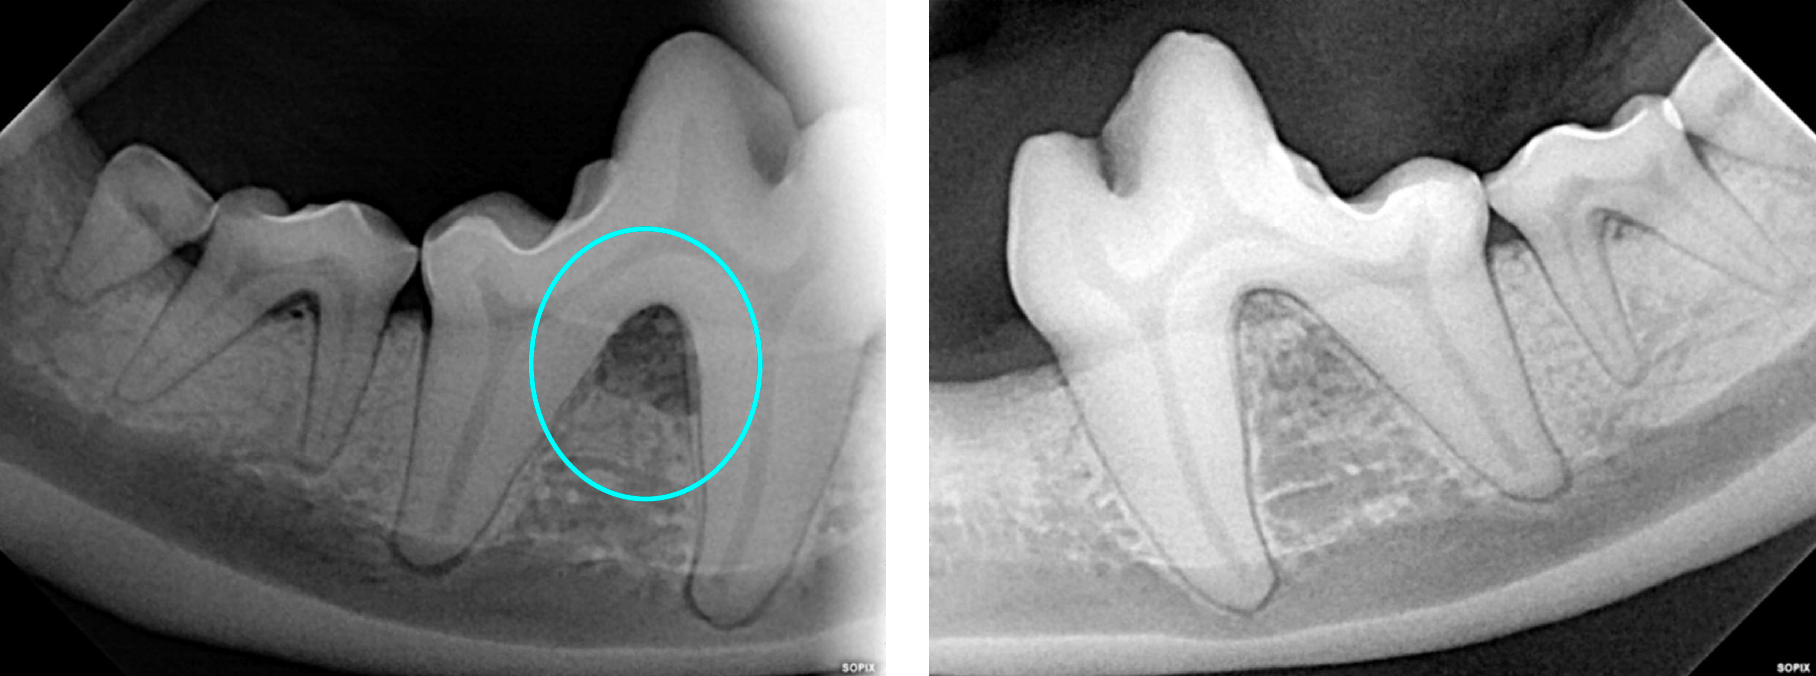

Below: Imaging of both sides of the lower right 4th premolar

Furcation exposure level 2 indicating bone loss under the crown